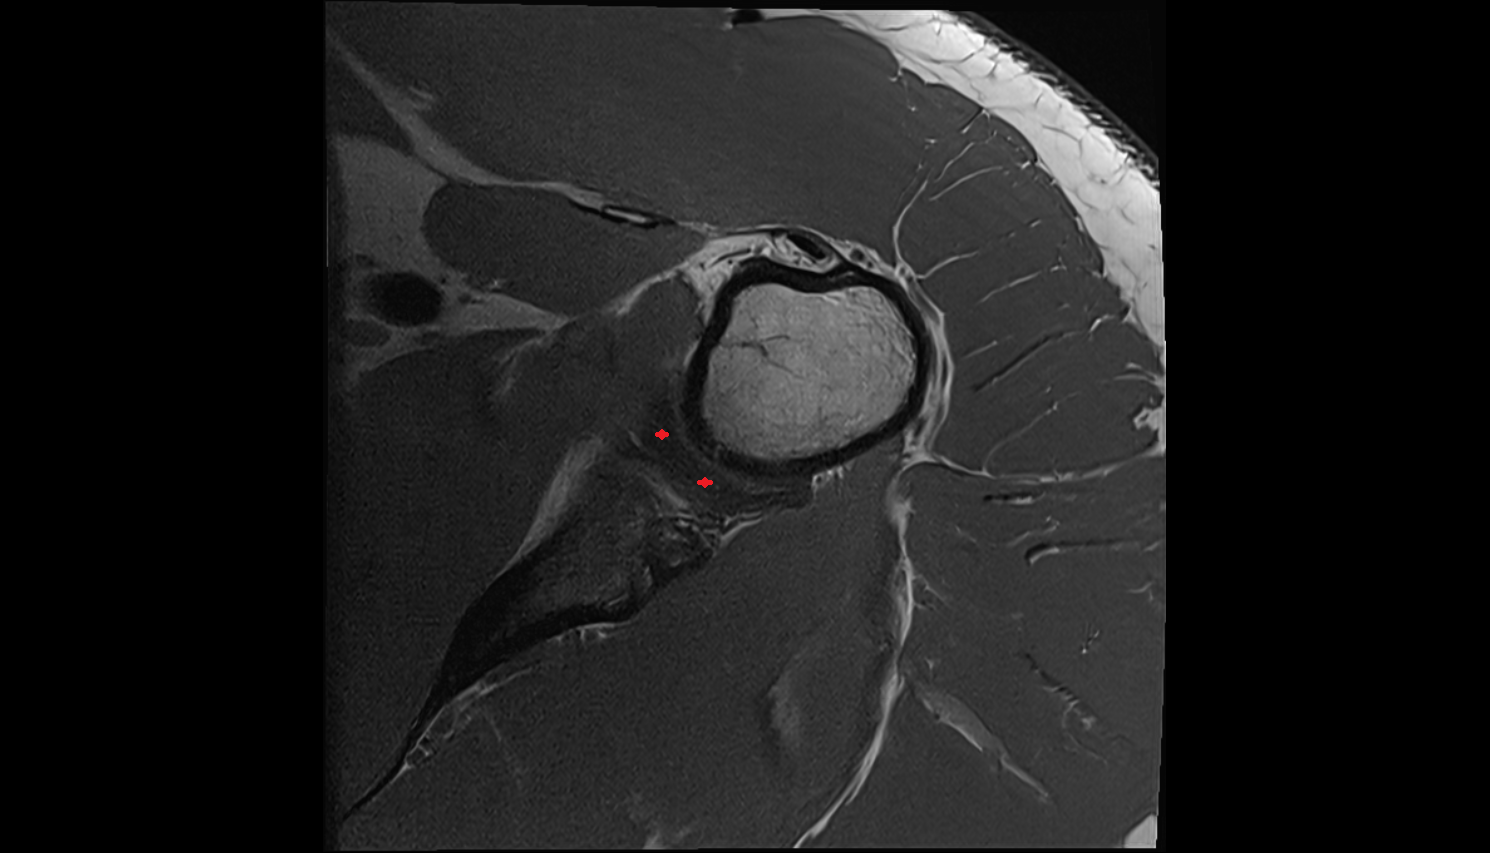

- Glenoid fossa

- Head of humerus

- Glenoid labrum

- Shoulder joint (glenohumeral joint)